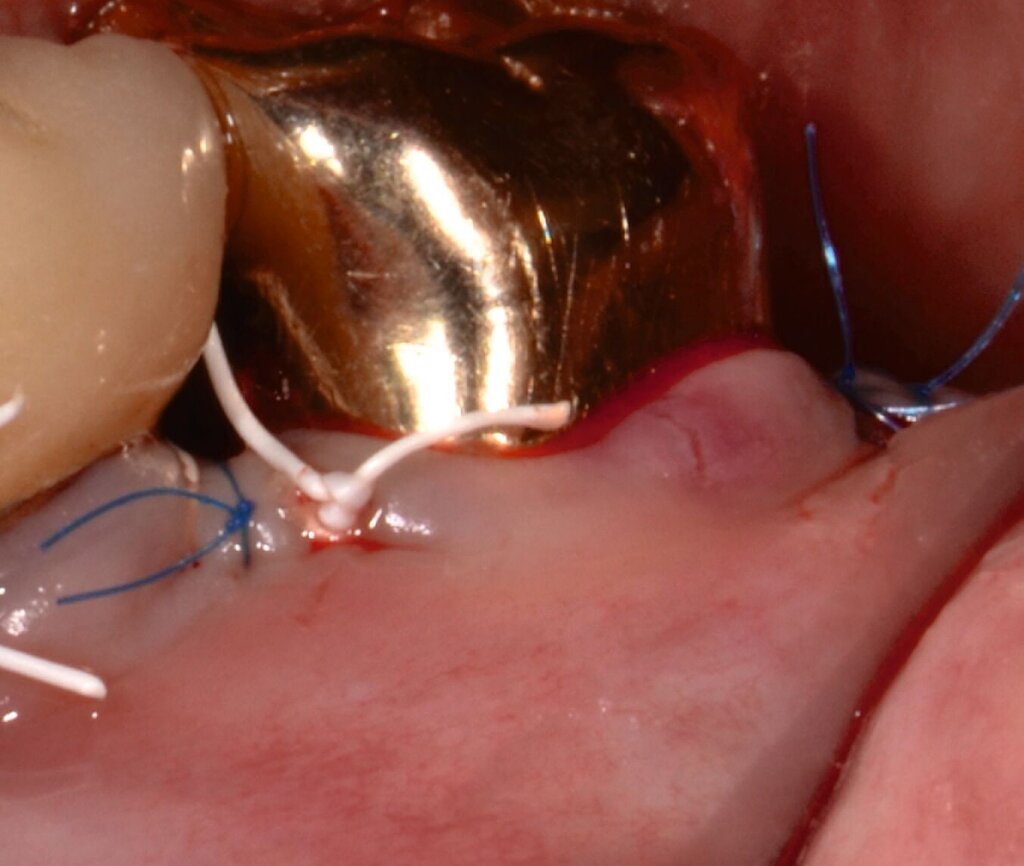

Alternativ kann eine GTR-Barrieremembran mit oder ohne zusätzlichen Defektfüller appliziert werden. Die Barrieremembran wird mit einer resorbierbaren Umschlingungsnaht befestigt, um den Furkationseingang abzudecken und die Wund- und Koagulumstabilisierung zu fördern. Um eine vollständige Abdeckung der Barriere zu ermöglichen, kann das Periost durchtrennt werden, um den Lappen leicht koronal zu verschieben. Der Lappen wird mit einer Umschlingungsnaht und Einzelknopfnähten über den vertikalen Entlastungsinzisionen oder mit interdentalen Nähten im Fall eines lateral extendierten Lappens in einer koronalen Position gesichert. Der Patient wird angewiesen, für einen Zeitraum von bis zu vier Wochen auf die mechanische Plaqueentfernung im Operationsgebiet zu verzichten. Während dieser Zeit werden Chlorhexidin-Spülungen oder -Gel verwendet. Der Patient kehrt zur Kontrolle der Wundheilung nach ein und zwei Wochen zurück, wenn die Nähte entfernt werden. Die Interdentalhygiene und die mechanische Plaqueentfernung werden nach vier Wochen wieder aufgenommen. Zudem wird ein individuelles Recallprogramm zur unterstützenden Parodontitistherapie (UPT) festgelegt.